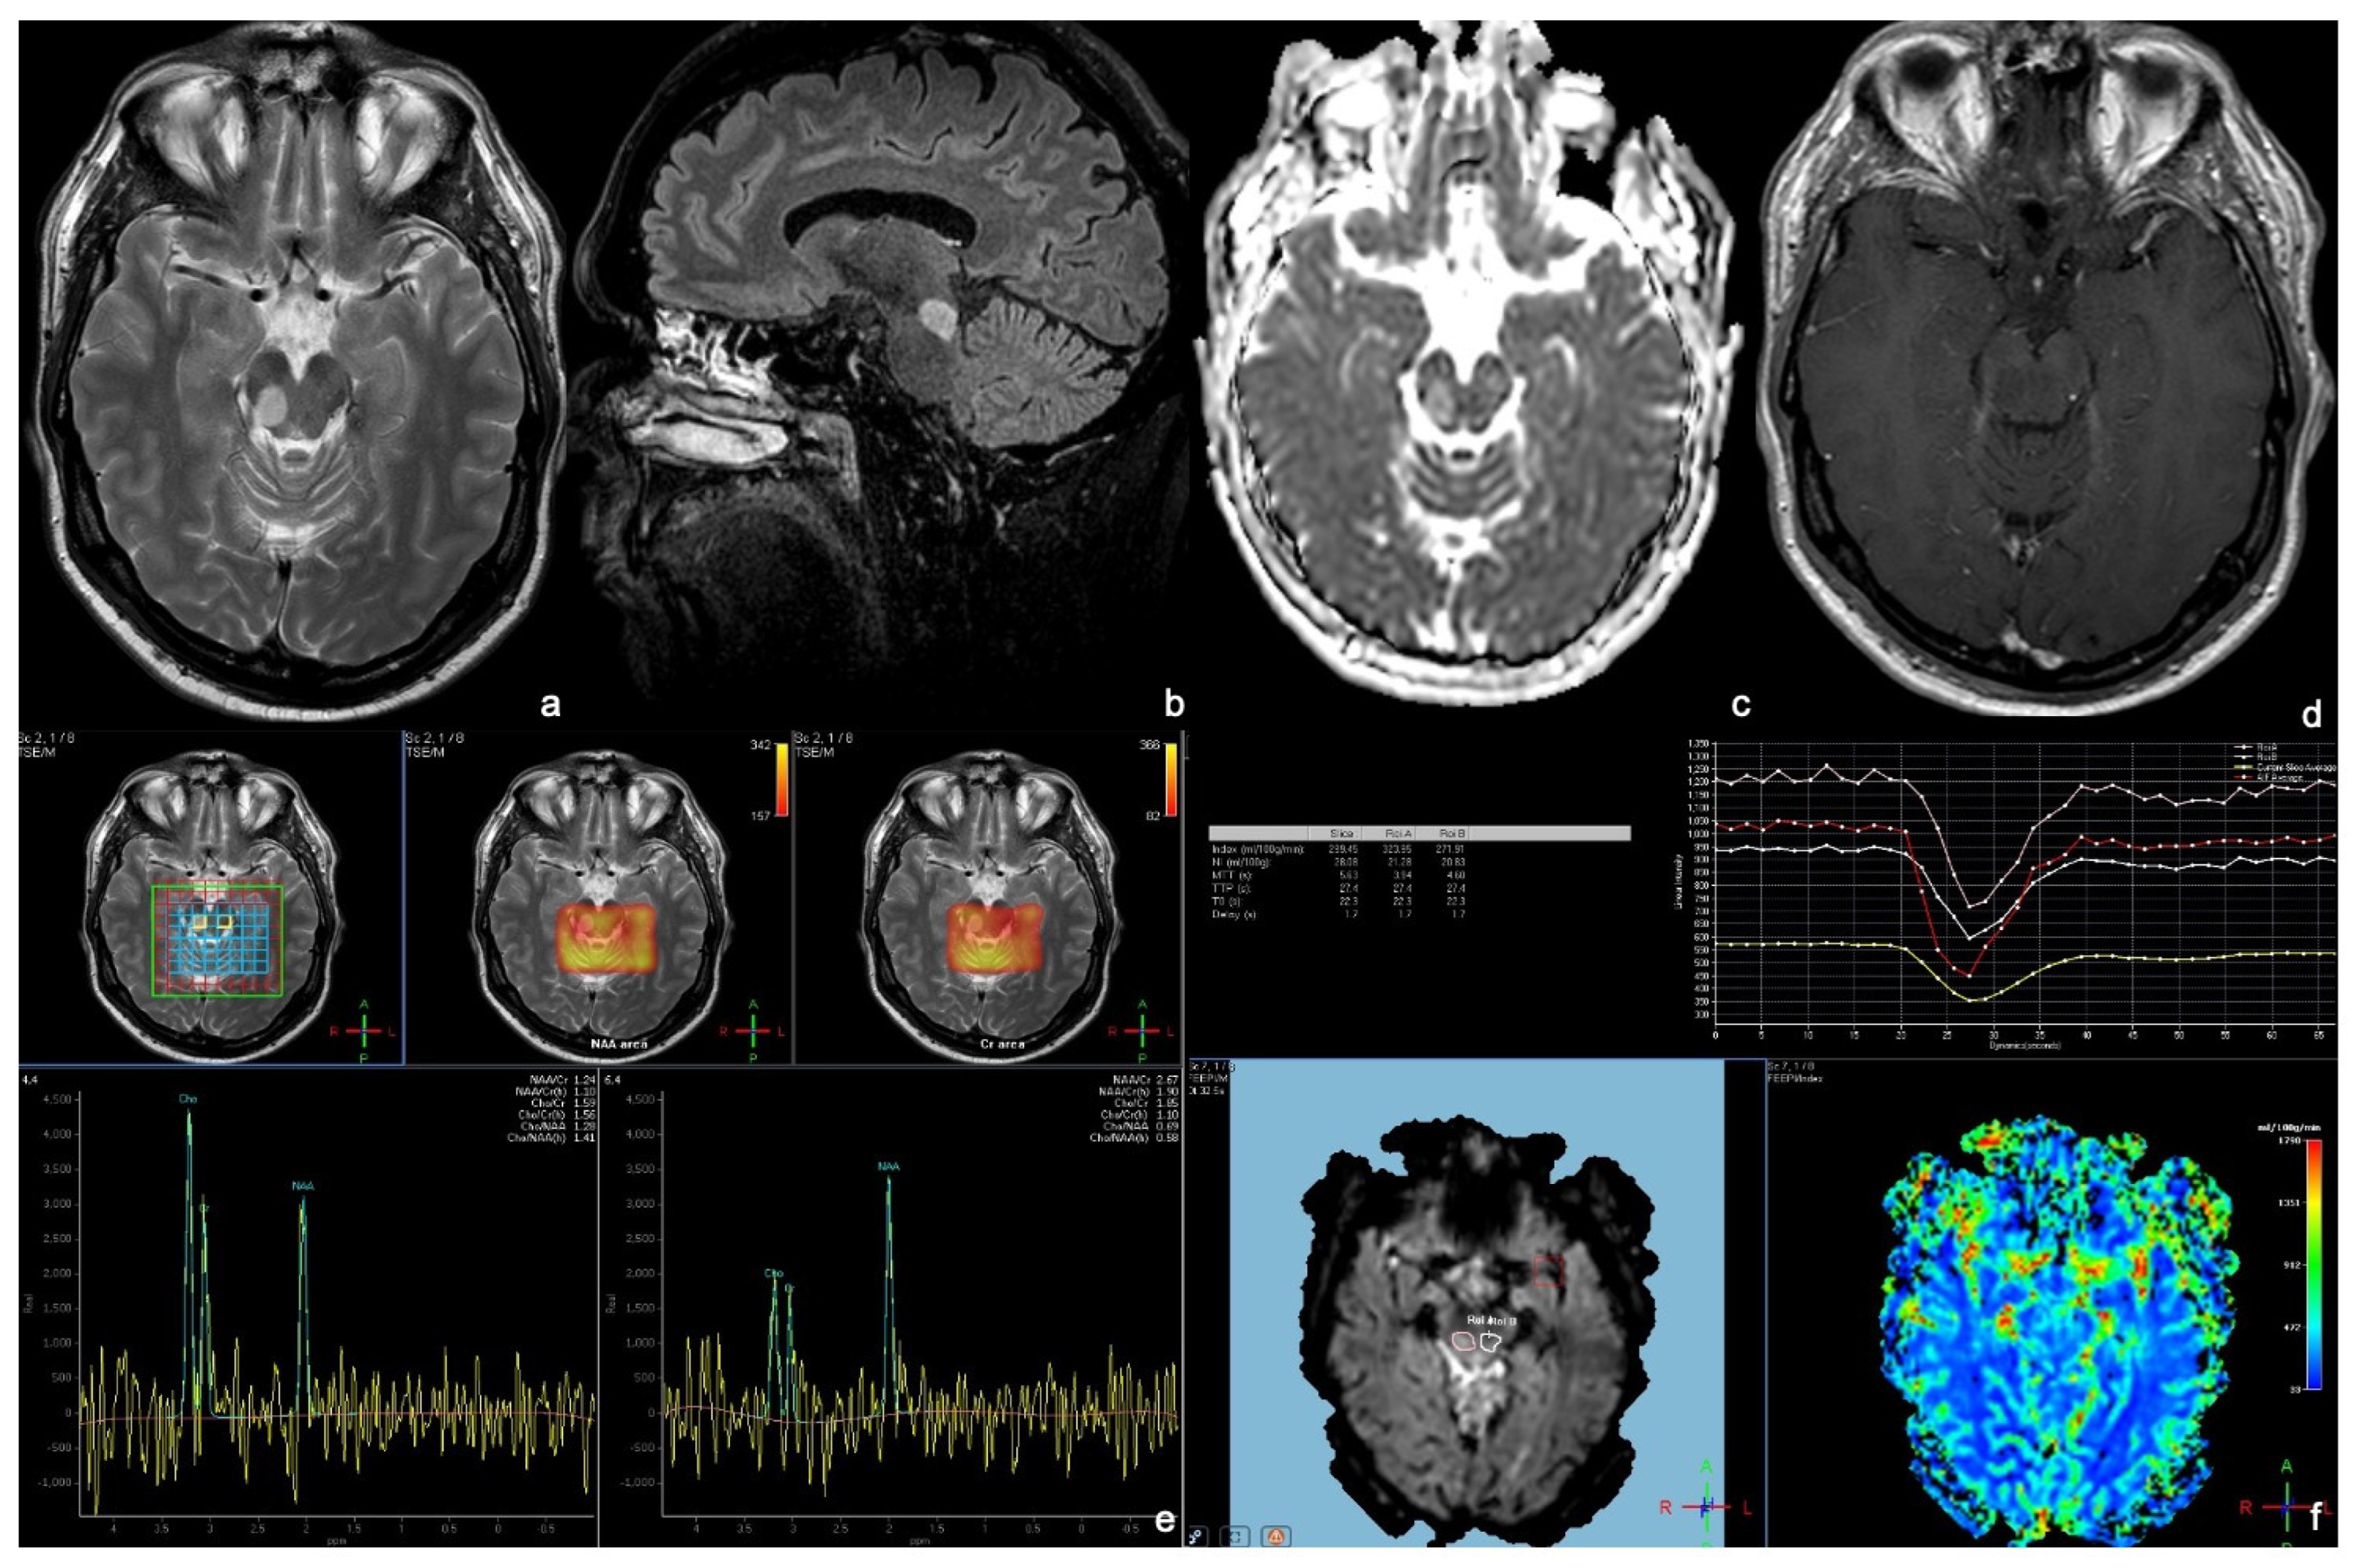

3.2. Enhancing Malignant Gliomas (EMGs)